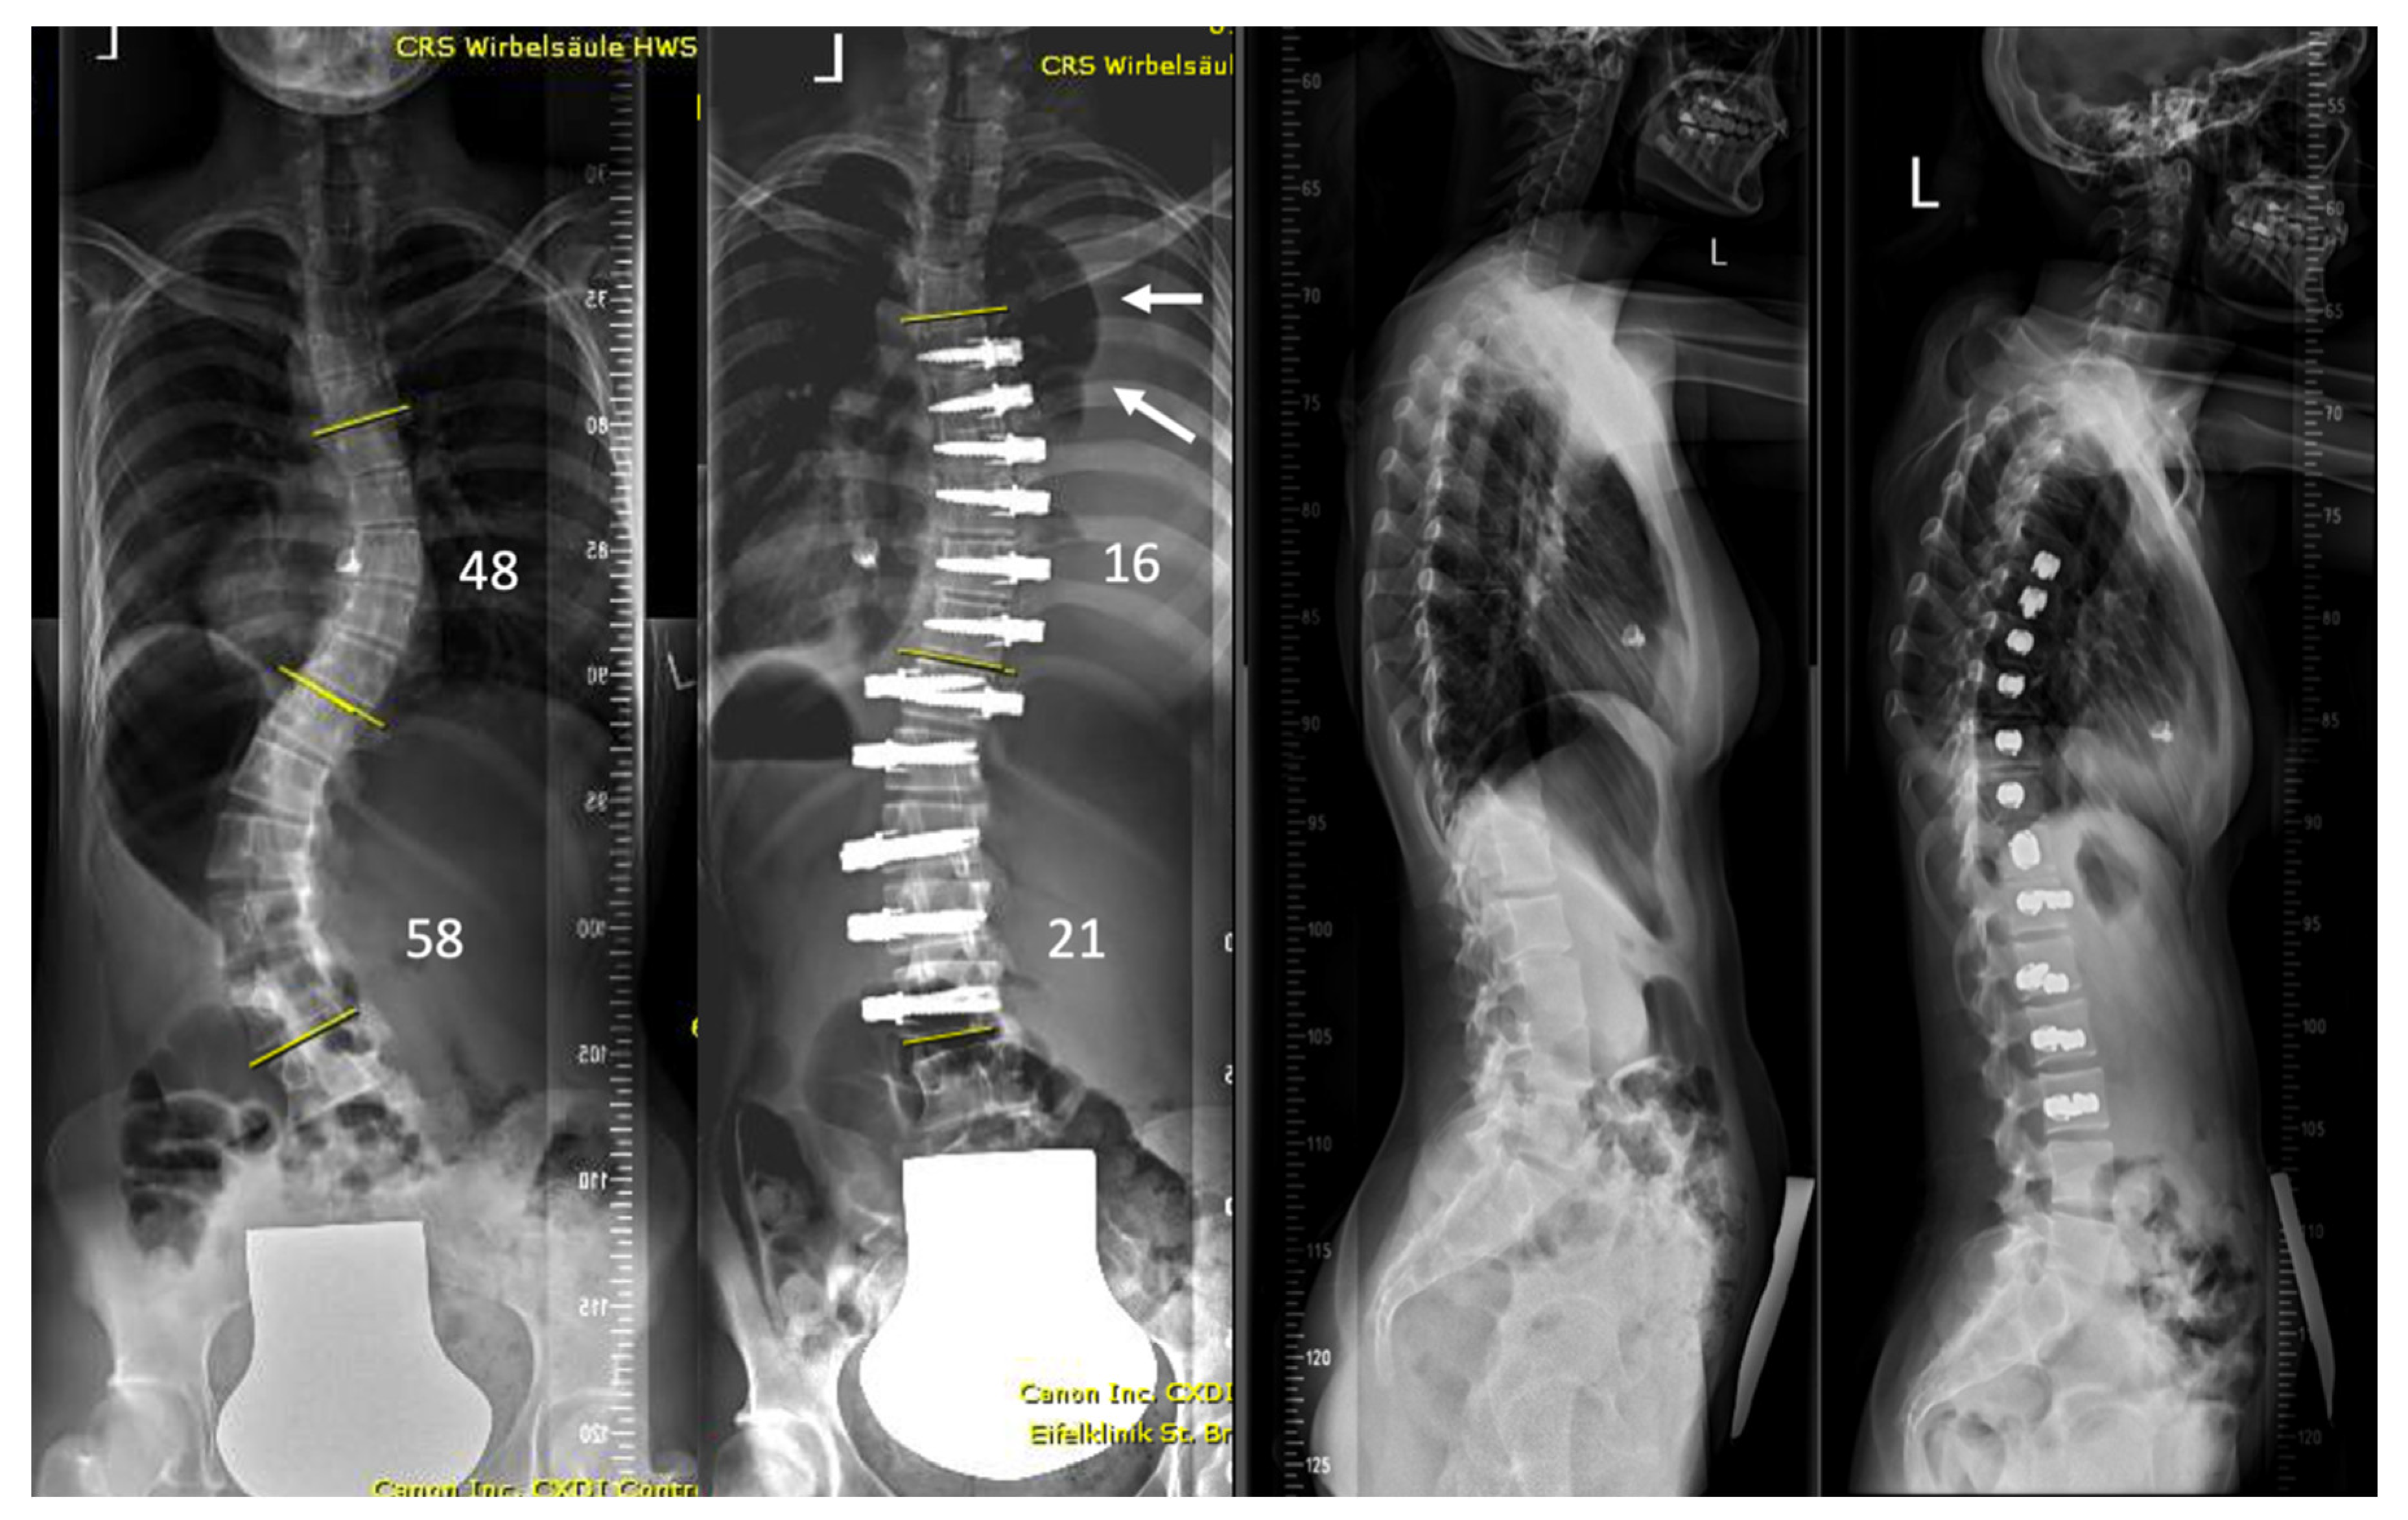

| 1 | 13.3 | F | 2 | T5-T12 right T12-L4 left | Pleural effusion | 2 weeks | Right | Minor dyspnea | Ultrasound, conservative treatment |

| 2 | 17.6 | F | 4 | T6-L1 right | Pleural effusion | 2 weeks | Right | Dyspnea, fatigue | 2 × aspiration |

| 3 | 16.2 | F | 4 | T5-T12 right | Contralateral atelectasis | 2 days | Left | Severe dyspnea | Re-intubation for 3 days, 3 bronchoscopies and removal of a mucus plug |

| 4 | 17.6 | M | 1 | T9-L3 right | Pleural effusion | 4 weeks | Right | Chest pressure | Chest tube reinsertion |

| 5 | 16.2 | F | 2 | T5-T11 right T11-L3 left | Pleural effusion | 3 weeks | Bilateral | Chest pain and elevated CRP levels | Bilateral aspiration, forced diuresis and i.v. albumin treatment |

| 6 | 17.7 | F | 2 | T5-T11 right T11-L3 left | Chylothorax | 3 days | Right | None effusion, diagnosed on routine post-op X-ray | Chest tube reinsertion and dietary restriction |

| 7 | 16.8 | M | 2 | T5-T11 right T11-L4 left | Pleural effusion | 3 weeks | Left | Unknown | Explorative thoracoscopy |

| 8 | 17.9 | F | 1 | T10-L3 left | Pleural effusion | 4 days | Left | None, effusion diagnosed on routine post-op X-ray | Aspiration followed by chest tube reinsertion for recurrent effusion |

| 9 | 14.6 | F | 2 | T5-T11 right T11-L4 left | Pleural effusion | 3 weeks | Right | Fatigue, dyspnea | Chest tube reinsertion, antibiotics for co-existing pyelonephritis |

| 10 | 14.3 | F | 1 | T11-L4 left | Pleural effusion with concomitant infection | 3 weeks | Left | Sudden sharp pain in the left chest and dyspnea | Attempted aspiration and chest tube without output. VATS and six weeks antibiotitcs because of postivie culture for staph epidermidis |

| 11 | 12 | F | 4 | T5-T11 right | Haematothorax | 1 day | Right | No symptoms, significant blood loss noticed after declamping the chest tube and drop of haemoglobin levels | Emergency explorative thoracotomy using the same surgical approach. No active bleeding found but clotted hematoma |

| 12 | 13 | F | 2 | T6-T12 right T12-L4 left | Haematothorax | 6 weeks | Right | Acute chest pain | Emergency explorative thoracotomy |

| 13 | 16.5 | M | 1 | T10-L4 left | Pleural empyema | 5 weeks | Left | Dyspnea, elevated CRP levels | VATS and antibiotic therapy |

| 14 | 16.3 | F | 2 | T5-T11 right T11-L4 left | Pleural effusion | 5 weeks | Right | Dyspnea | Aspiration |